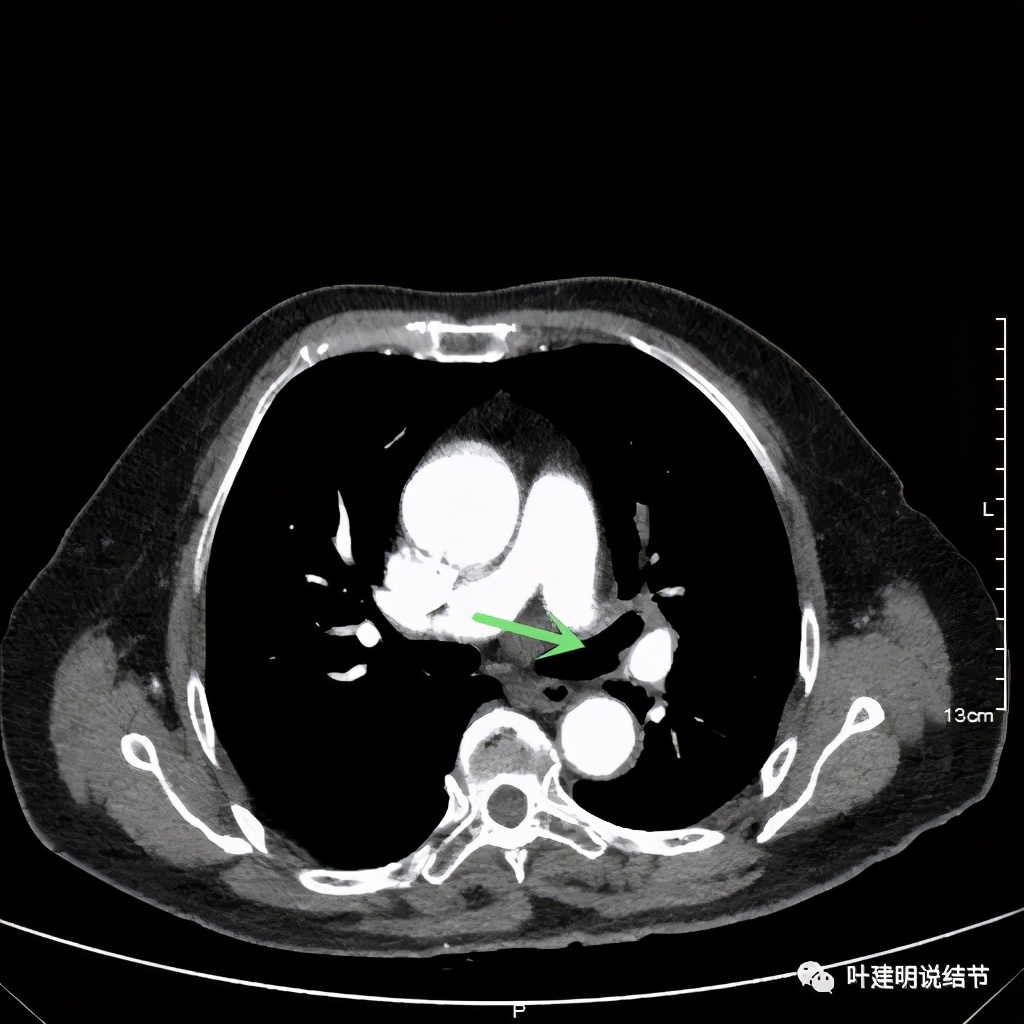

左上肺基本已经不见肿瘤,只在主动脉旁少许软组织影

上图示主动脉弓水平仍见软组织影